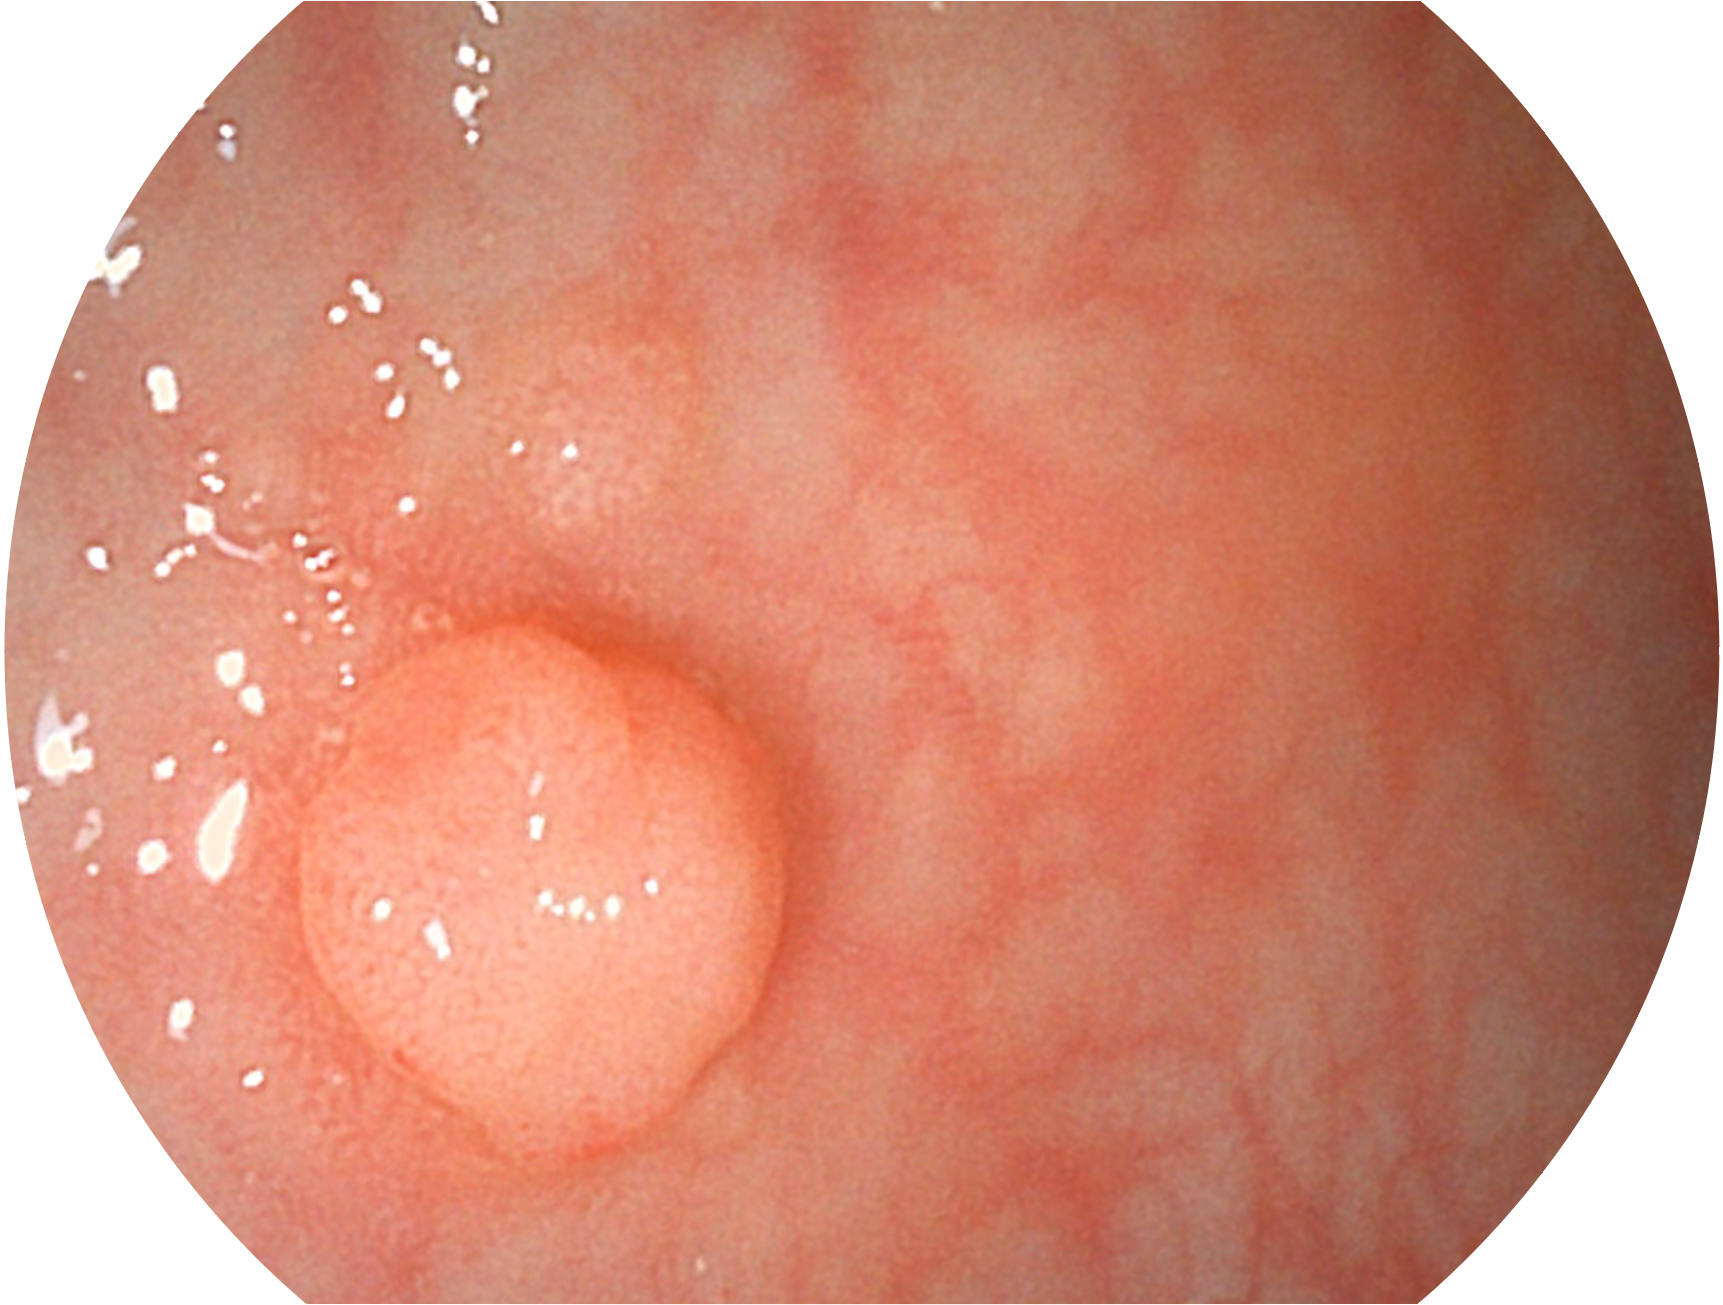

九州酷游新开发的内镜染色技术,主要是基于多波长LED 光源的开发,VLS-55Q 四波长LED 光源是由四个不同颜色的LED光按照相应照明模式所规定的特定发光比例进行合束后形成,合束后形成的照明光的光谱由红光、绿光、蓝光及蓝紫光这四个不同的波段范围构成。具有更高光谱自由度,通过光谱比例的控制,实现了聚谱成像技术,英文全称为“Spectral Focused Imaging, SFI”,缩写为“SFI”和光电复合染色成像技术,英文全称为“Versatile Intelligent Staining Technology, VIST”,缩写为“VIST”。